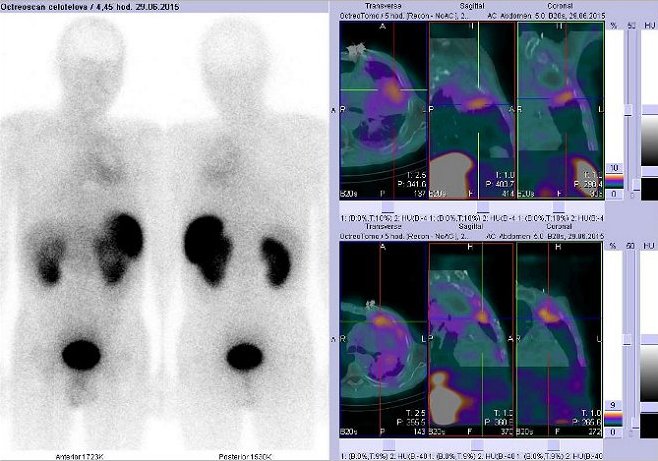

Pomocí dvoudetektorové hybridní tomografické kamery Symbia T2 (SPECT/CT) firmy Siemens opatřené kolimátory pro střední energie jsme provedli celotělovou scintigrafii a také cílenou tomografickou scintigrafii (SPECT) a CT a fúzi obrazů SPECT/CT hrudníku za 4 hod.

(obr. 2 - 3) a 24 hod. (obr. 4 - 16) po i.v. podání 220 MBq analogu somatostatinu značeného

111In (přípravek OctreoScan firmy Mallinckrodt Medical).

/ Obr.č.2: Celotělová scintigrafie v přední a zadní projekci – 2x s různou modulací obrazů. Vyšetření 4 hod. po aplikaci radioindikátoru.

/

/ Obr.3: Celotělová scintigrafie a fúze obrazů SPECT a CT – vyšetření hrudníku. Vyšetření 4 hod. po aplikaci

radiofarmaka.

Vždy nad sebou: vlevo transverzální řezy, uprostřed sagitální řezy, vpravo koronární. Vpravo nahoře i dole zaměřeno na ložisko v levé plíci.

Kromě fyziologické depozice radioaktivity v játrech, slezině, tračníku, v ledvinách a močovém měchýři pozorujeme chabě zvýšenou depozici radiofarmaka v levém středním plicním poli, při došetření 24 hodin od aplikace RF je akumulace v levém plicním křídle zřetelněji patrná. Na tomogramech je zřejmé, že se jedná o viabilní akumulující lem kaudálně kolem rozsáhlého infiltrativního zastínění v horním plicním poli vlevo, kromě tohoto lemu je patrná ještě velmi chabě zvýšená depozice radioaktivity dorsobazálně v dolním laloku, kde v CT obraze možné sekundární zánětlivé změny? V pravém plicním křídle bez průkazu patologické akumulace RF. Závěr: Nález svědčí pro přítomnost viabilního lemu mírně zvýšené denzity somatostatinových receptorů kolem rozsáhlé patologické neakumulující léze v levém horním plicním poli (centrální fotopenická oblast). Chabě nespecificky zvýšená akumulace RF v oblasti levé plicní baze dorsálně nejspíše odpovídá chronickým zánětlivým změnám v této lokalizaci.

U pacienta jsme scintigrafickým vyšetřením Octreoscanem prokázali lem nádorové tkáně s mírně zvýšenou hustotou somatostatinových receptorů kolem rozsáhlé patologické neakumulující léze v levém horním plicním poli.